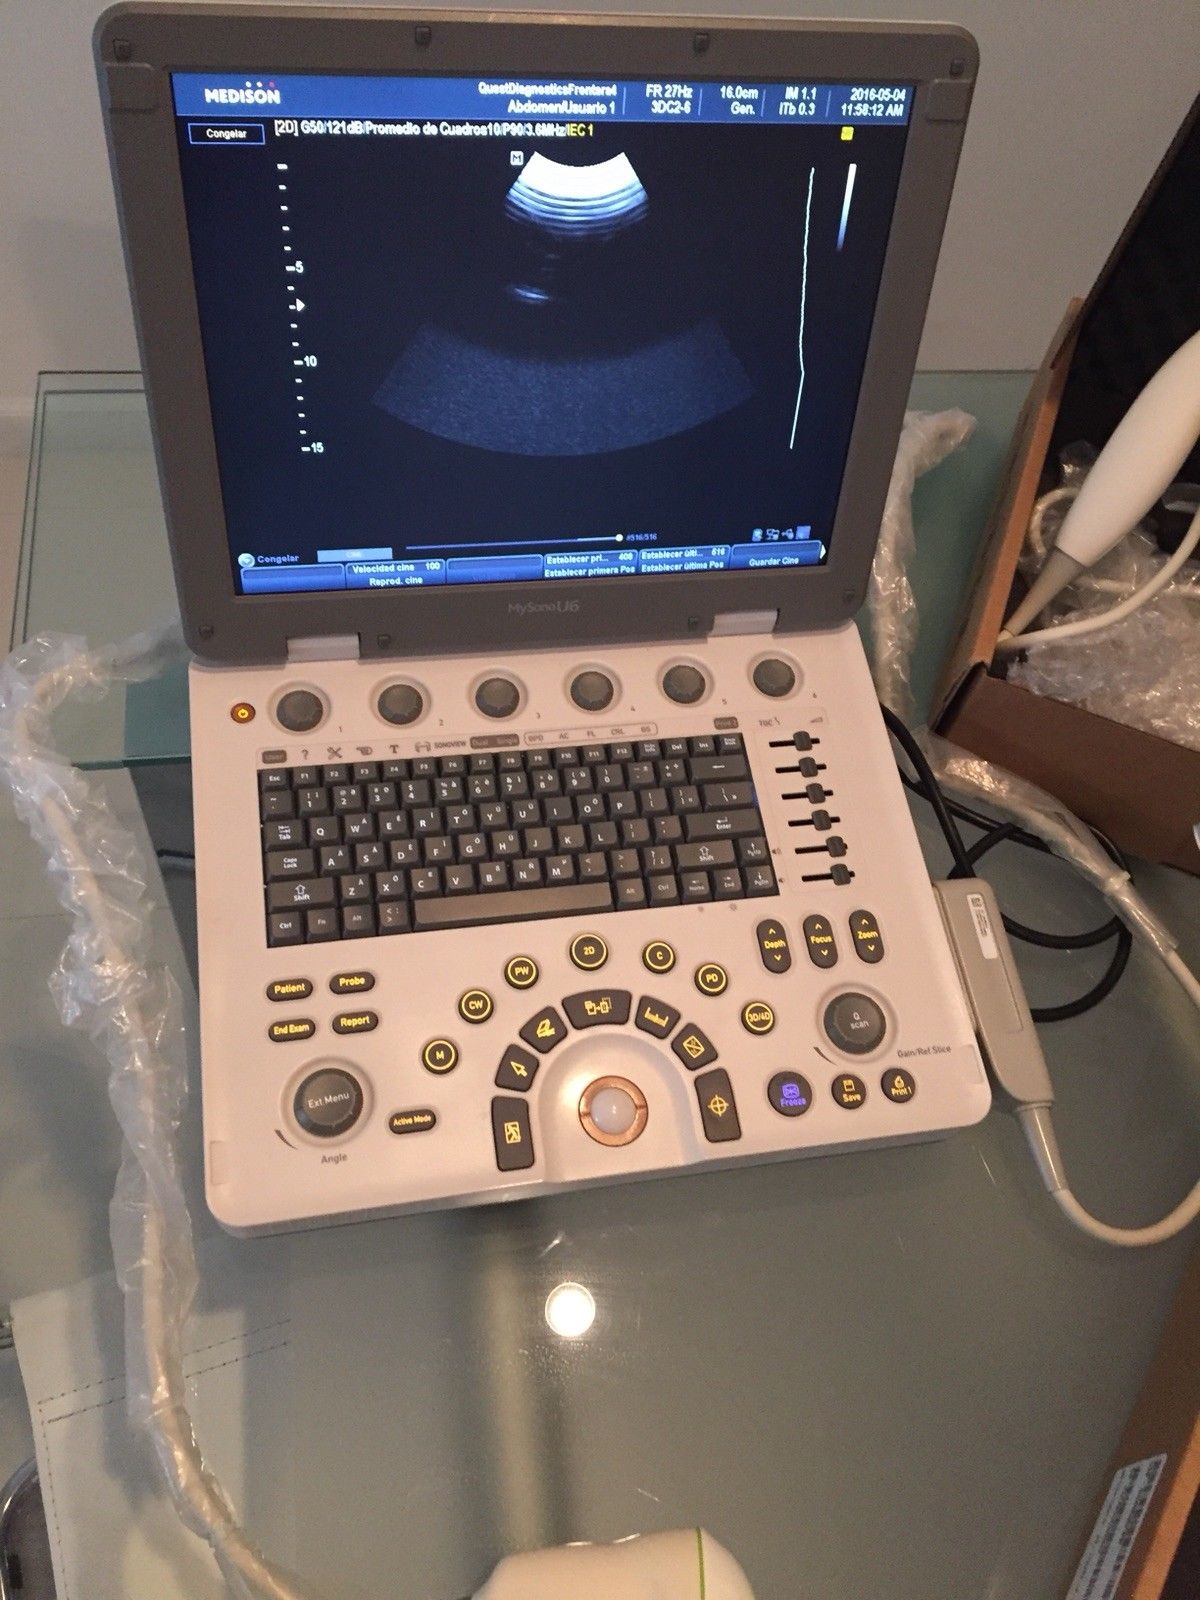

SAMSUNG HM70A PORTABLE ULTRASOUND WITH 2 PROBES

Sale price$ 11,150.88